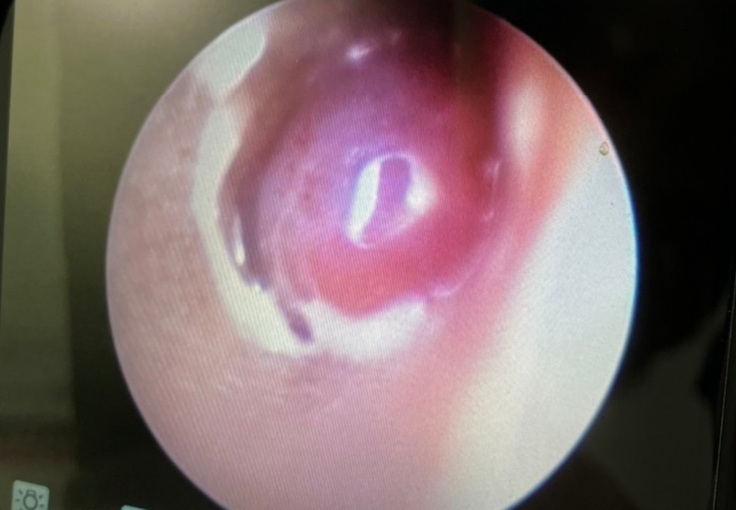

【ぎん君】は8日に予定通りCTと肉腫の切除の手術になりました。

耳の中を見ると大きな出来物?が見受けられたとのことで肉腫なのか異物なのかを確認してから、焼きながら切除とのことでした。

傾きやよろけがあることから内耳や中耳にも何らかの異常があるとして、外耳よりも内耳や中耳の様子の確認がメインになるとおっしゃって、内耳や中耳に異常の度合いにより内科的な処置、もしくは外科的な処置をしていくか判断するとして手術に入られました。

手術の結果としては外耳に腫瘍がありそちらを少しずつ取り除いていただきました。

一枚目は手術前、2枚目は切除あと。

ただ問題は鼓膜近くの見えている外耳の腫瘍ではなく、その先。つまり鼓膜の中、中耳の鼓室から腫瘍が派生していると思われるとのこと。

鼓膜を破っての腫瘍の派生とのこと。